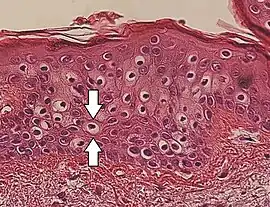

Vacuolization is the formation of vacuoles or vacuole-like structures, within or adjacent to cells. Perinuclear vacuolization of epidermal keratinocytes is most likely inconsequential when not observed in combination with other pathologic findings. In dermatopathology "vacuolization" often refers specifically to vacuoles in the basal cell-basement membrane zone area, where it is an unspecific sign of disease.[1] It may be a sign of for example vacuolar interface dermatitis, which in turn has many causes.

It is one of the components of koilocytosis, which may be present in potentially pre-cancerous cervical, oral and anal lesions.[2]